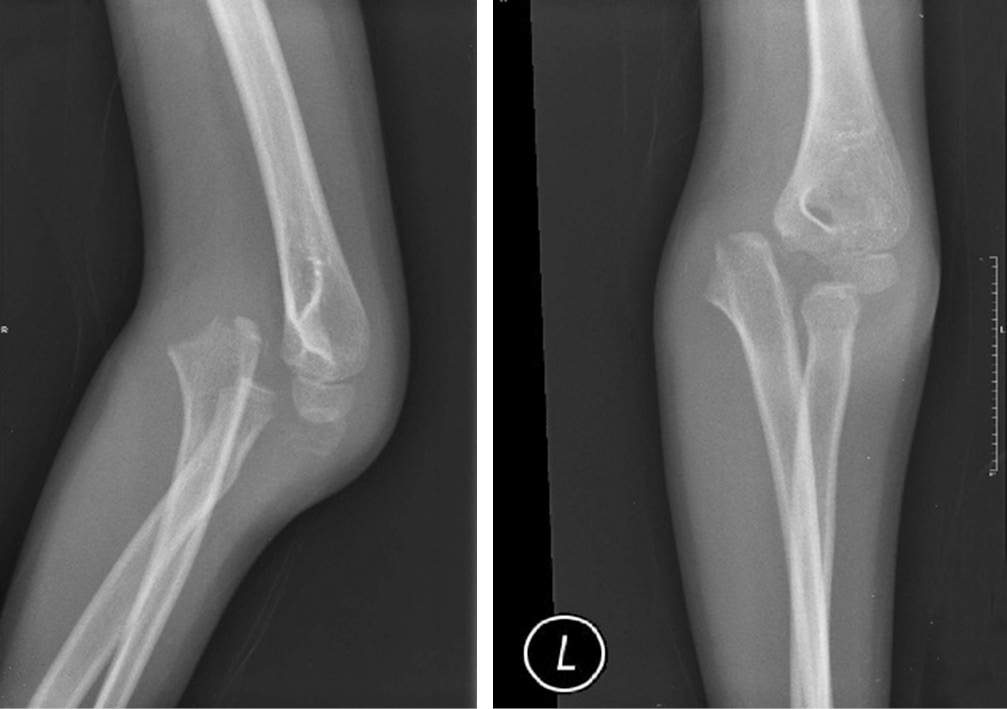

Онемение безымянного пальца и мизинца уменьшилось через неделю после операции. Симптом «когтеобразной кисти» исчез через 2 нед. Перелом зажил, и спицы Киршнера были удалены через 6 нед. (рис. 3). Осторожные пассивные движения в локтевом суставе начаты через 4 нед. с последующим присоединением активных движений через 6 нед. после операции. Лонгета была снята через 6 нед. Через 8 нед. был достигнут полный объем движений в локтевом суставе. Отмечена стабильность локтевого сустава при варусном и вальгусном стресс-тестах. Пациентка смогла вернуться к своей повседневной деятельности, и в данный момент находится под наблюдением с осмотром раз в 3 мес. (рис. 4).

Рис. 3. Перелом сросся через 6 нед. после операции